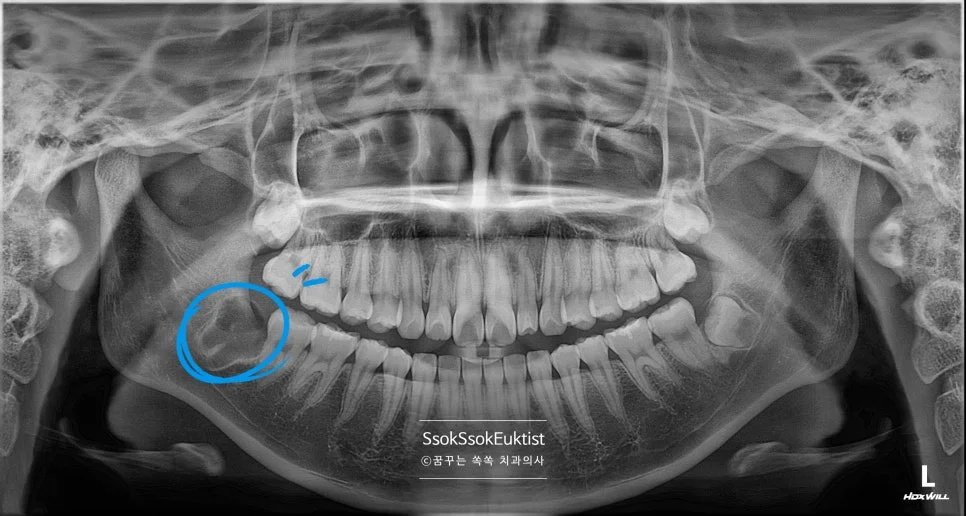

중간 난이도 완전 매복 사랑니 파노라마 엑스레이

잇몸 하방에 완전히 묻혀 있는 완전 매복 사랑니입니다. 사랑니가 맹출 하면서 잇몸의 통증을 호소하는데요, 뒤의 턱뼈와의 공간이 부족하여 어차피 매복될 치아라 바로 발치를 말씀드립니다.

깊숙이 매복되어 있어 잇몸 절개를 하고, 치아 상방의 치조골을 일부 삭제를 하고, 잘 나올 수 있게끔 사랑니 머리를 분리한 후 발치를 시행합니다.

CBCT 3차원 영상 — 사랑니와 신경관의 인접 관계 확인

발치 전 CT를 보면 신경관과 맞닿아 있어 발치 난도가 높은 케이스임을 알 수 있습니다.